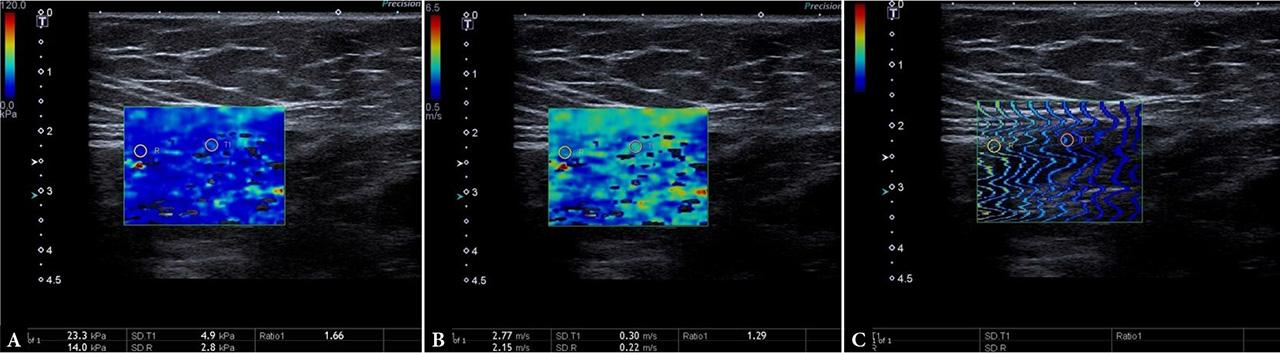

Informed written consent was obtained from the parents or legal representatives of all participants. Ethics approval was granted by the local ethics committee at the university, and a consent form was obtained from each participant of the study (09/03/2020-1628). This prospective observational study was performed by gray-scale US and SWE in pediatric patients with UDT between January 2019 and December 2020. Patients with non-palpable UDT, retractile and ec-topic testes, endocrine diseases, systemic diseases, and incomplete data were excluded from the study. All testes were examined using an ultrasound scanner (Toshiba/Canon, Japan), which supports B mode gray-scale US and SWE modalities (Fig. 1). SWE images were viewed using three display modes: elasticity mode (kPa) (A), speed mode (m/s) (B), and propagation mode (C) (Fig. 2).

Shear wave elastography (SWE) images in a 120-month-old boy with UDT. A. Elasticity mode 23.3 kPa kilopascals (kPa). B. Velocity mode 2.77 meters per second (m/s). C. Propagation (arrival time contour) mode parallel lines taken for confirmation

The transducer was placed onto the skin surface over the testes with light contact, using ample coupling gel to avoid a compression effect, and was kept stationary during acquisitions for SWE examination. The optimal axial or longitudinal images were obtained via SWE examination. SWE measurements were performed away from the mediastinum of the testis. SWE values were measured in the longest longitudinal plane using a circular region of interest (ROI). After freezing, SWE images were viewed using three display modes: speed mode in meters per second (m/s), elasticity mode in kilopascals (kPa), and propagation (arrival time contour) mode (Fig. 2). We hypothesized that this approach increased the accuracy of the numerical values obtained. Tissue stiffness was displayed on a chromatic scale with progression from blue to red, which indicated stiffness values from low to high. The observer adjusted the chromatic scale in the range of 0–30 (kPa) and 0.5–5 (m/s) to perform the interpretation optimally, since the stiffness value of testicular parenchyma is considerably low compared to the other organs. The stiffness values were calculated using Young’s modulus and recorded in m/s and kPa as units (Dewall RJ. Elastic value) E (kPa) is calculated using the equation E = 3ρ (m/s)2 (ρ refers to tissue density, with approximated value in human body defined as 1 g/cm3, and m/s refers to shear wave propagation velocity)(15). The average stiffness values of the testes were derived from three separate 2–4 mm diameter ROIs, which were placed in the testicular parenchyma (upper, central, and lower region). The ROIs were placed on the stiffness areas in the testicular parenchyma regions as determined by the quantitative values displayed during examination for SWE imaging. Stiffness was measured in meters divided by seconds (m/s) with the ROI technique in three different areas on the testicle, and maximum and average values were recorded accordingly (Fig. 2). SWE was obtained as three separate images for each testis, which were quantitatively analyzed. The average of these three measurements was then determined as the SWE value of the testes. The SWE values of the UDT were compared with the SWE values of the adjacent soft tissue measured at the same level, and the elastography ratio was calculated. Thus, our aim was to increase the accuracy of the obtained numerical values. It was essential to keep the probe stationary over the testes without compression for a few seconds until a complete color map was obtained. The average time devoted to each patient’s examination was approximately 10 minutes to avoid the risk of variability in shear-wave speed measurements.